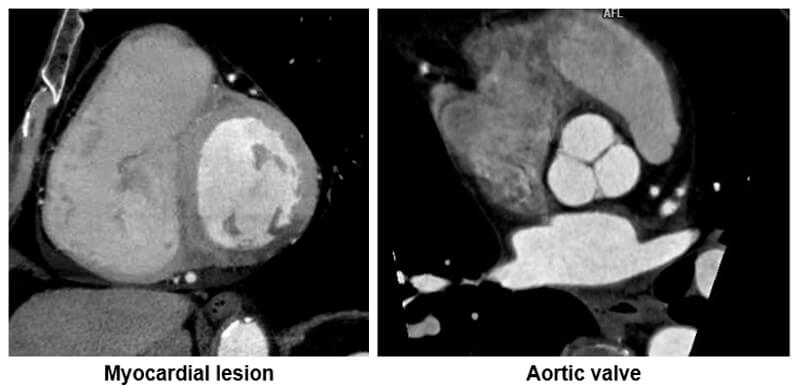

Heart

The minimum intensity algorithm is particularly useful in highlighting hypo or low dense regions within the heart.